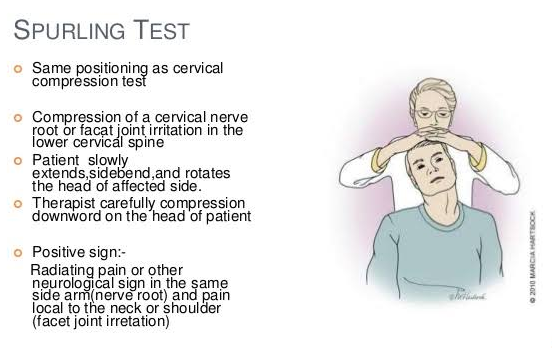

Valsalva test Procedure: The patient is seated with the thumb in the mouth and attempts to push the thumb out by blowing out hard. Assessment: The pushing increases the intraspinal pressure, revealing the presence of space-occupying masses such as extruded intervertebral disks, tumors, narrowing due to osteophytes, and soft tissue swelling. This leads to radicular […]